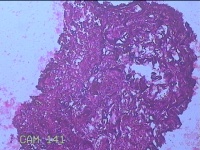

性别

女

年龄

45岁

临床诊断

四肢皮脂腺囊肿

一般病史

发现右侧大腿结节半年余。

标本名称

右侧大腿结节

大体所见

灰白暗红色组织1.5x1x0.8cm一块,表面带梭形皮肤1.3x0.7cm,皮下见结节1.3x1x0.7cm一个,切开结节呈实性,切面灰白 暗红色,质软。

图2